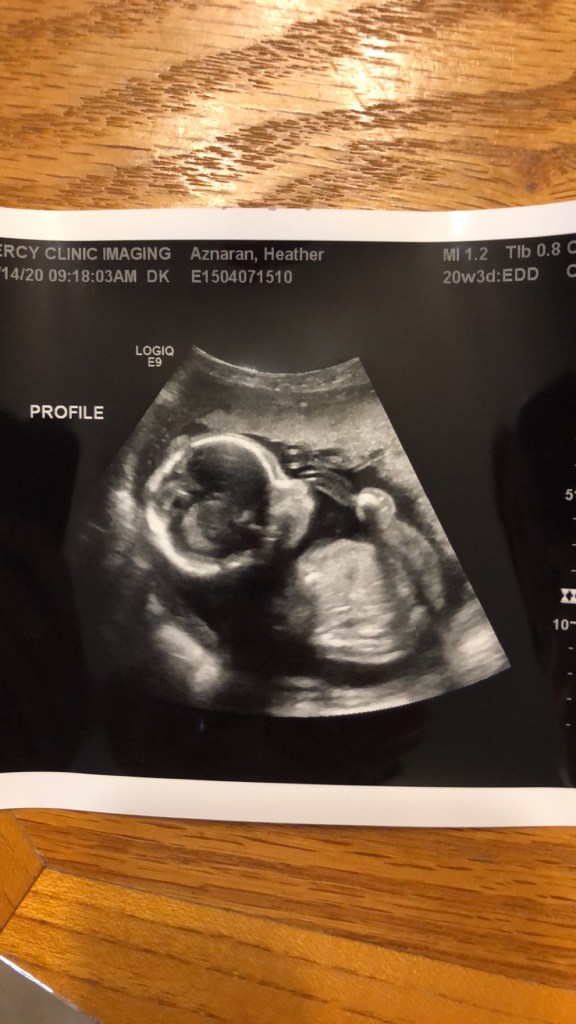

Another virus caused you to have many health problems. CMV. It is a virus that is minor in its effects to adults, but most often fatal for unborn babies. At 24 weeks and 5 days God decided to rescue you from this virus. Once you were born the meds were administered to stop CMV in its tracks. But the damage done was irreversible. At least that is what we were told.

Yes. It is confirmed by MRIs that you have microcephaly and only 40% of your brain mass. (See Ultra-sound photo above)